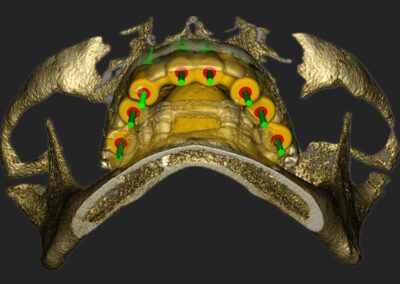

Bilder v.l.n.r.: 01 Herstellung der röntgenopaken Schablone zur Übertragung auf den Dicom-Datensatz / 02 Planung der Zahnimplantatstellung anhand der röntgenopaken Schablone / 03 Virtuelle Planung auf dem 3D-Modell / 04 Übertragung der Röntgenschablone auf dem Dicom-Datensatz (1:1) / 05 Virtuelle Plaung im Dicom-Datensatz / 06 Visualisierung frontal / 07 Visualisierung seitlich / 08 Visualisierung des Implantat-Falles frontal / 09 Visualisierung mit Bohrschablone

Ein entscheidender Bestandteil dieser modernen Praxis ist die Auswertung von 3D-Daten, die aus der Computertomographie extrahiert werden. Neuere Entwicklungen zeigen auch, dass Daten von optischen Scannern zunehmend in den Planungsprozess integriert werden. Diese umfassenden Informationen, kombiniert mit fortschrittlicher Implantatplanungssoftware, ermöglichen eine akkurate Simulation sowohl chirurgischer als auch prothetischer Phasen.

Vor der eigentlichen Operation können Implantatpositionen sorgfältig festgelegt werden, wobei spezifische Faktoren wie das Knochenvolumen und die -qualitäten, die Lage anatomischer Strukturen (wie Nerven, Gefäße und Nebenhöhlen), prothetische und ästhetische Bewertungen sowie präzise Messungen der Breite und Höhe des Knochens an den vorgesehenen Implantatstellen berücksichtigt werden. Auch die Abstände und Winkel zwischen den Implantaten lassen sich exakt berechnen, was entscheidend für den langfristigen Erfolg der Behandlung ist.

Ein weiterer Vorteil dieser Technologie ist die Möglichkeit der dreidimensionalen Positionierung der Implantate, die entscheidend für optimale klinische Ergebnisse ist, insbesondere in Bezug auf ästhetische Gesichtspunkte. Die geführte Implantatchirurgie (GIS) ermöglicht es, vorher geplante Rehabilitationsprojekte direkt und präzise in das chirurgische Feld zu übertragen. Dies fördert nicht nur die Genauigkeit, sondern kann auch dazu beitragen, eine minimal-traumatische oder lappenlose Operation durchzuführen.

Durch Matching von DICOM- und STL-Datensätzen entsteht ein vollständiges dreidimensionales Patientenmodell.

Dies ermöglicht:

• Exakte Beurteilung des Knochenvolumens

• Darstellung kritischer anatomischer

Strukturen (N. mandibularis, Sinus

maxillaris)

• Analyse der prothetischen Emergenzprofile

3. Simulation und chirurgische Umsetzung

Moderne Planungssoftware erlaubt:

• Virtuelle Implantatinsertion

• Kollisionsanalysen

• Simulation augmentativer Maßnahmen

• Planung navigierter oder schablonengeführter Chirurgie

Die digitale Planung kann direkt in eine CAD/CAM-gestützte Bohrschablone überführt werden, wodurch die intraoperative Umsetzung hochpräzise erfolgt.